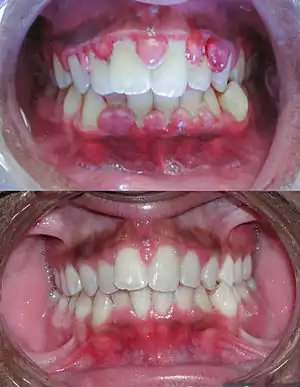

| Severe gingivitis before (top) and after (bottom) a thorough mechanical debridement of the teeth and adjacent gum tissues | |